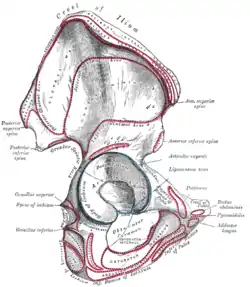

Right hip bone. External surface., with pectineal line corresponding to the "Pectineus" area demarcated in red at right. | |